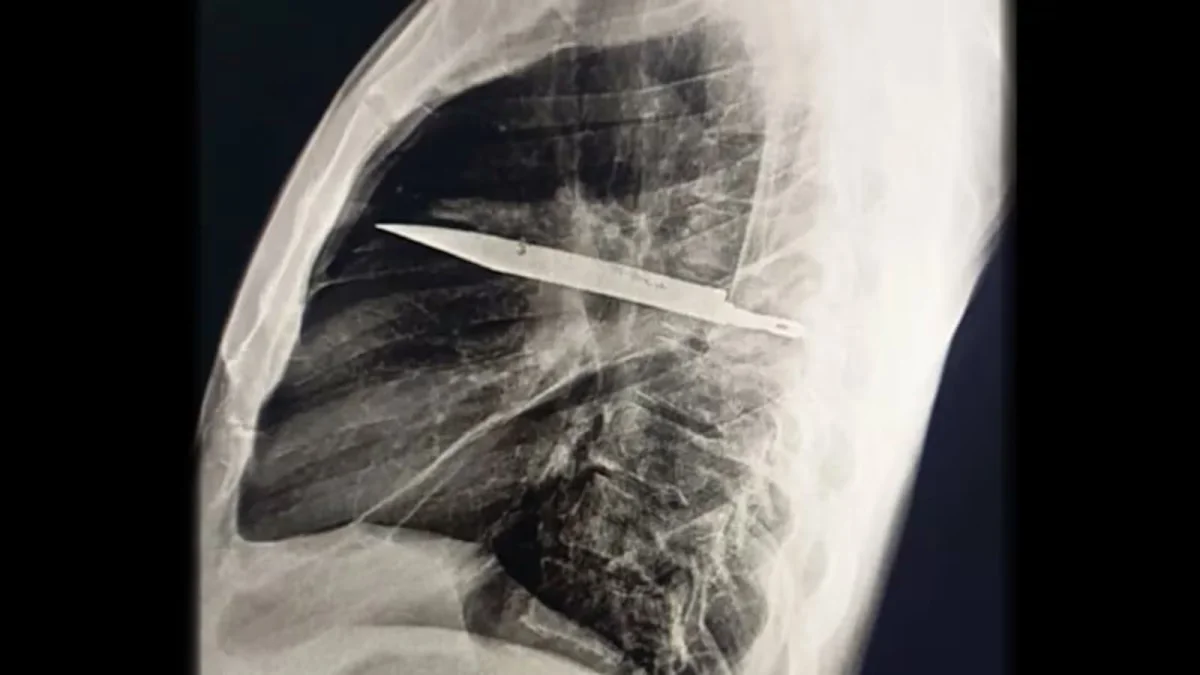

Reprodução/Journal of Surgical Case Reports

Da Redação – Um homem de 44 anos, morador da Tanzânia, descobriu recentemente que carregava uma lâmina de faca presa no peito havia oito anos. O caso veio à tona depois que ele procurou atendimento médico devido à presença de secreção na região torácica.

Exames de imagem revelaram que o objeto estava alojado entre as costelas, sem atingir órgãos vitais. Os médicos explicaram que o corpo do paciente criou uma cápsula fibrosa em torno da lâmina, mecanismo de defesa que isolou o material e evitou complicações mais graves.